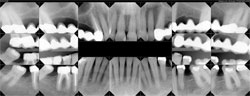

A 50-year-old male complained of loose upper four-unit bridges placed 15 years ago and sensitivity of anterior teeth. An examination revealed recurrent caries of the terminal abutments of both restorations (Figure 3). Dental history included extraction of both distal terminal abutments of the previous three-unit bridges due to caries and failed endodontics. They were replaced with the currently failing fixed partial dentures. Teeth Nos. 20 and 31 had been previously extracted due to fracture. The medical history included maxillary sinus antrostomies to relieve chronic sinusitis approximately 20 years earlier. Social history included several cigars daily.

Figure 1 Profile smile. |  Figure 2 Tilt-down smile.  Figure 3 Full-mouth radiographs. Note location of maxillary sinuses, as well as mesial angulation of teeth Nos. 19 and 32. | |||||